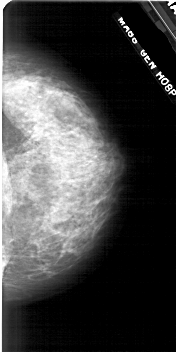

A_1712_1.RIGHT_MLO

RIGHT_MLO LINES 5401 PIXELS_PER_LINE 2581 BITS_PER_PIXEL 12 RESOLUTION 43.5 NON_OVERLAY